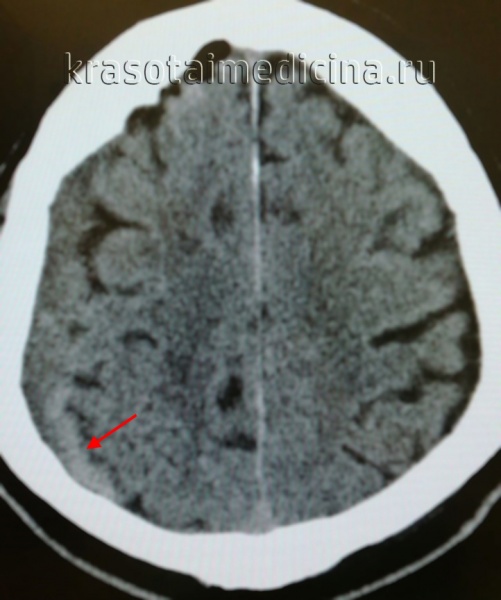

КТ головного мозга. Геморрагический инсульт, обширная интрапаренхиматозная гематома в левой гемисфере

Они позволяют определить объем и локализацию внутримозговой гематомы, степень дислокации мозга и сопутствующего отека, наличие и область распространения кровоизлияния. Желательно проведение повторных КТ-исследований, чтобы проследить эволюцию гематомы и состояние мозговой ткани в динамике.